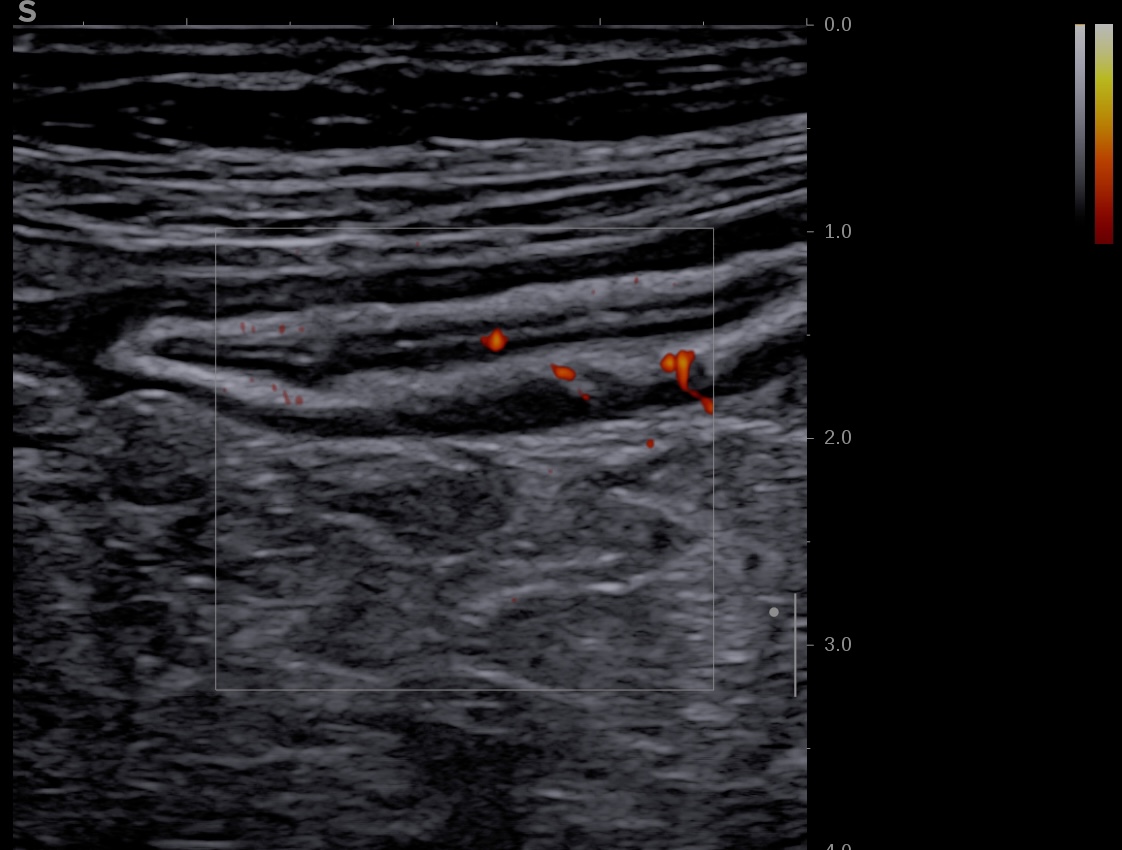

Activité Doppler limitée à la paroi, intense

- spots longs et multiples (limités à la paroi)

- Limberg 2 signaux nombreux et plus longs dans la paroi Vascularisation modérée avec plusieurs signaux Doppler visibles dans la paroi intestinale, (= inflammation modérée)